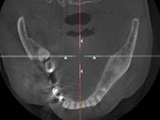

① 3Dによる画像診断

CTにて撮影した3Dデータをもとに、歯肉、骨、神経を総合的に校了した診断が可能なシステムです。